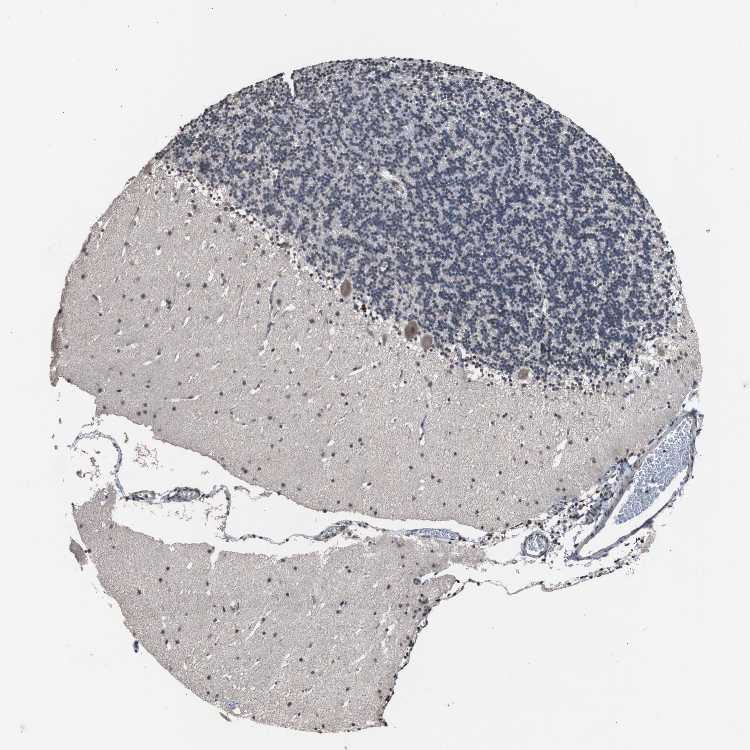

BRAIN CEREBELLUM Show tissue menu

CEREBELLUM - Expression summary

CEREBELLUM - Antibody stainingi

Antibody staining in the annotated cell types in the current human tissue is reported as not detected, low, medium, or high, based on conventional immunohistochemistry profiling in selected tissues. This score is based on the combination of the staining intensity and fraction of stained cells.

Each image is clickable and will lead to virtual microscopy that enables deeper exploration of all samples and also displays staining intensity scores, fraction scores and subcellular localization as well as patient and tissue information for each sample.

Antibody HPA007002

Purkinje cells Low

Cells in granular layer Not detected

Cells in molecular layer Not detected